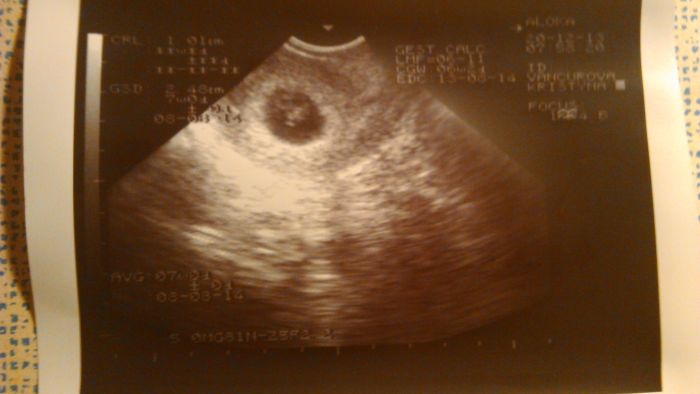

Ahoj holky,tak mám za sebou kontrolu u doktora :) Všechno je v pořádku podle doktora sem 7+0 miminko má centimetr srdíčko buší ukázkově a malé se má k světu. TeĎ ještě genetika a budem to mít vybojovaný. Prej sem se svou diagnozou učebnicový případ a doktor měl ze mě obrovskou radost :) Tatínek se nám už ani neozval,take se zařídíme spolu sami a nějak to zvládneme!Ale budoucí babi s dědou slaví a strašně se na mimo těší! Přikládám první fotečku prcka :*